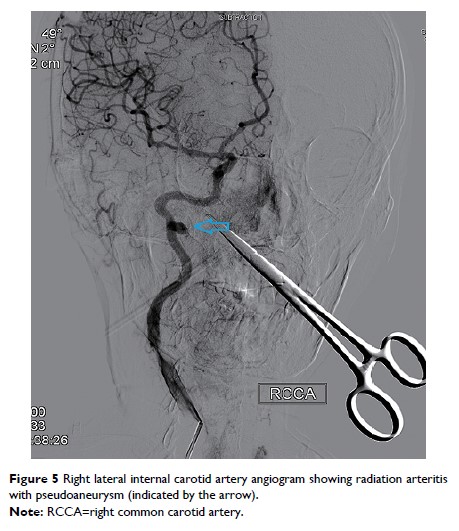

- 作者:Lina Tang, Yijie Chen, Zhongshi Du, Zhaoming Zhong, Qin Chen, Lichun Yang, Ruoxia Shen, Yan Cheng, Zizhen Zhang, Ehui Han, Zhihong Lv, Lijun Yuan, Yong Yang, Yinrong Cheng, Lei Yang, Shengli Wang, Baoyan Bai, Jun Luo

- 期刊:Cancer Management and Research